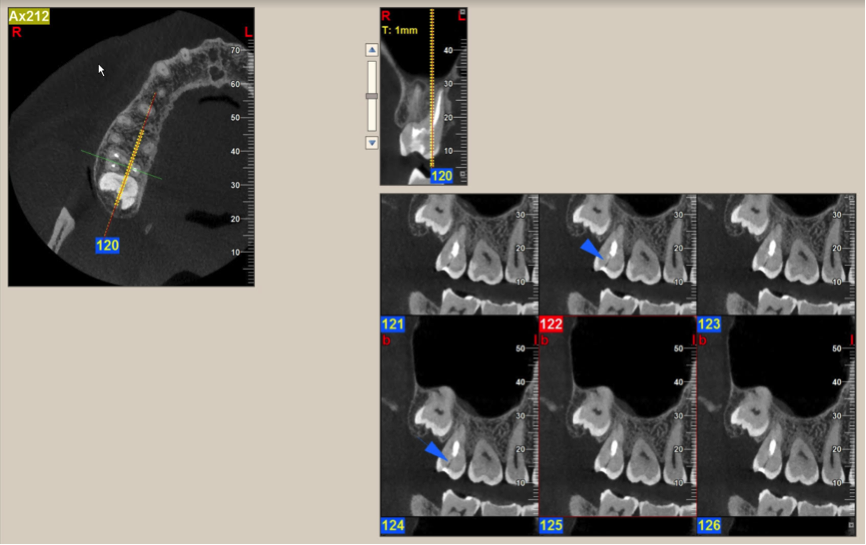

The imaging protocol establishes the proper technical parameters to allow for the best images to be acquired based on the special needs of the patient and the specific diagnostic concerns. For example, how large or small should the area of exposure (field of view) be? What level of image detail is required? Since almost all of the CBCT scanners currently on the market offer a range of fields of view, it is in the best interest of our patients to select one that will permit full assessment of the region of interest without missing anything or exposing too large of an area (Figure 1). The potential size of the pathological entity under investigation and the extent of the affected region will dictate the field of view necessary.4 A larger field of view should be selected when facial symmetry is to be investigated or skeletal anomalies that may require radiologic assessment of a large portion of the head. In most other cases, a single- or a dual-arch scan (or an even smaller field of view, such as 40 mm X 40 mm or 50 mm X 50 mm) is adequate for the evaluation of an area limited to 2 to 3 teeth or a quadrant of the jaw.

When there is a need for extra detail, a high-resolution (small voxel size) protocol should be selected. Contemporary CBCT machines can acquire imaging volumes with voxel sizes as low as 0.08 mm, which produces a highly detailed image. This type of protocol is excellent for diagnostic tasks such as the detection of possible ankylosis of an impacted tooth and possible root fractures or root resorption.5

(1.) Limited field of view, high resolution (0.125 mm voxel size) scan of the right maxilla for the assessment of tooth #2, which was symptom- atic. Note the thin radiolucent line indicating a longitudinal fracture.

Figure 1